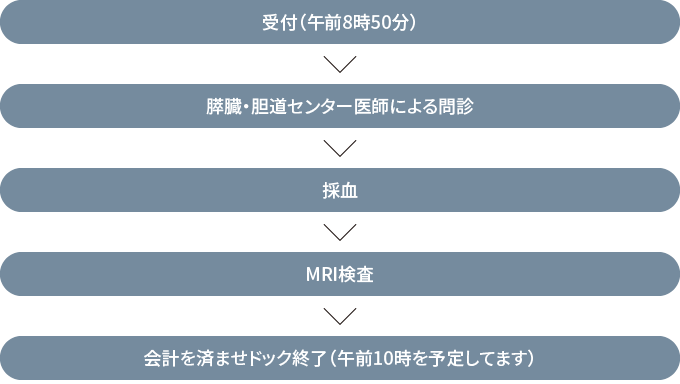

問診、採血、MRI、により膵がん、胆道がんの可能性のある方をスクリーニングします。

17,600円(税込)

(糸魚川市民の45歳以上の方には、糸魚川市より半額の補助が出ます。申し込み時にお申し出ください。)

(1日1名の予約枠です)